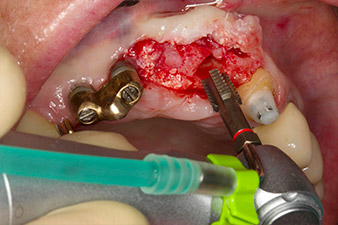

След първичното оздравяване, меките тъкани са оформени посредством базално разположения мост. Два месеца по-късно, обработваното поле е изложено на палатинална алвеоларна инцизия (Фиг 2). Размерите на алвеоларната кост са достатъчни в позиция 22. Фигури 2 и 4 показват препарацията на имплантното ложе, нарязващия винт и имплатирането, използвайки Implantmed.

С цел да се компенсира периодонталната загуба на кост и да се постигне естетически добър резултат, имплантирането е комбинирано с водена костна регенерация (GBR) с ксеногенен заместващ материал и колагенова мембрана (Фиг. 5 и 6).